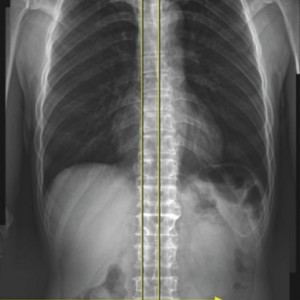

엑스레이 검사

좌우 골반 수평 및 비틀림 측정

흉추, 요추 만곡, 척추 휘어짐 측정

좌우 다리 길이와 틀어짐 측정

엉덩이 관절의 염전각 측정

경골의 회전과 내반 측정